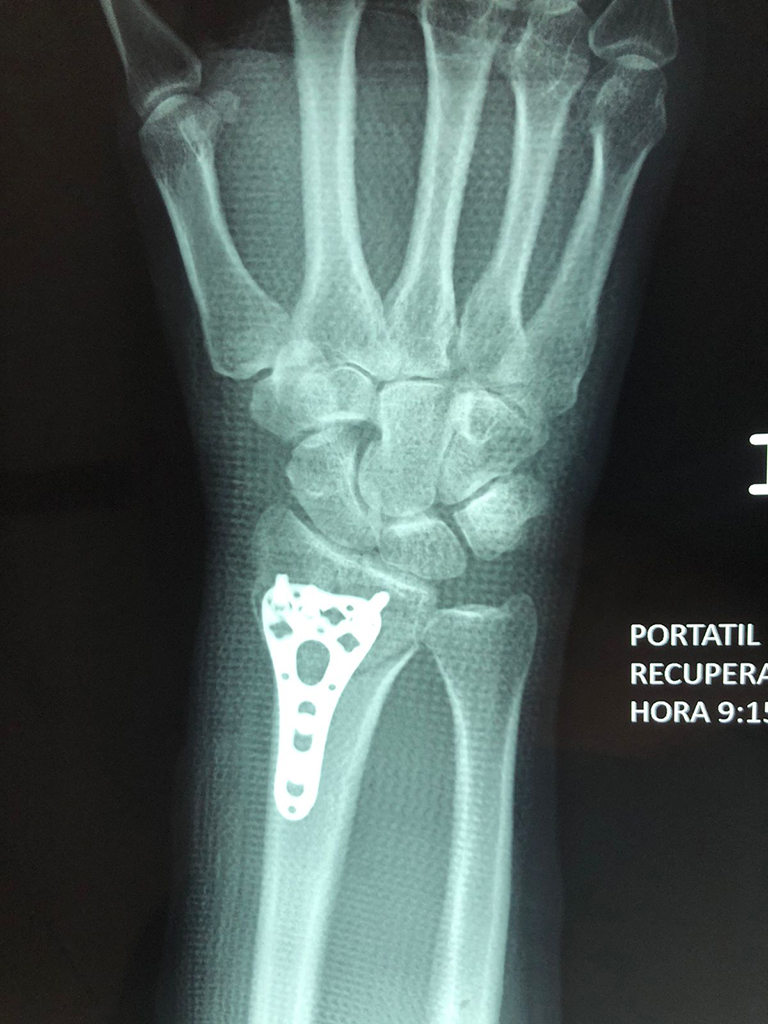

Cirugía de Fémur - Cirugías de Muñecas y Manos

Los procedimientos más comunes en cirugía de la mano son aquellos destinados a reparar traumatismos, incluyendo lesiones de tendones, nervios, vasos sanguíneos, y articulaciones; huesos fracturados; y quemaduras, cortes, y otros daños de la piel.